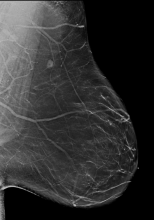

AI is also helping simplify complex tasks and help reduce the reading time on involved exams. One example of this is in 3-D breast tomosythesis with hundreds of images, which is rapidly replacing 2-D mammography, which only produces 4 images. Another example is automated image reconstruction algorithms to significantly reduce manual work. AI also is now being integrated directly into several vendors' imaging systems to speed workflow and improve image quality.

In addition to women with dense breasts, there are also other women for whom mammographic screening is not really enough, which is why research needs to continue in this field. Dr. Wendie Berg, a leading breast cancer specialist, talks with ITN about new research and advancements in breast imaging technology.

Dr. Berg, MD, PhD, FACR, FSBI, is Professor of Radiology at the University of Pittsburgh School of Medicine and Magee-Womens Hospital of UPMC, specializing in breast imaging. She is also the Chief Scientific Advisor to DenseBreast-info.org. A renowned expert, she writes and co-edits one of the leading textbooks on the topic, Diagnostic Imaging: Breast, currently in its third edition, and has co-authored over 120 peer-reviewed research publications.

Breast Density | April 14, 2023

It has long been said that a national reporting standard is needed in order to ensure all American women receive at least the same basic information regarding breast density, and a spotlight put on the importance of routine breast imaging. Dr. Wendie Berg, a leading breast cancer specialist, shares with ITN what is being done in the fight against breast cancer and the importance of this standardization in reporting for women.